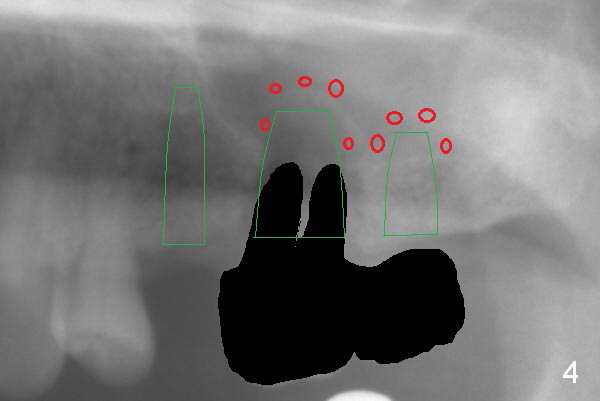

The 72-year-old man will return for #13-15 implantation after that at #2/4 and 28. There is severe wear in the cingula of the upper anterior teeth due to posterior collapse (several missing teeth, residual root and failing restoration, Fig.1). Prior to removal of the cantilever bridge (#14.15), an implant is placed at #13 (Fig.2). If the defect at #14 is too large after extraction, an implant is placed at #15 with an immediate provisional bridge (Fig.3 white line). Otherwise a large implant (possibly Tatum tapered) will be placed at #14 (Clindamycin) with splinted immediate provisional (Fig.4). Allograft is expected for sinus lift at #14 and 15 (Fig.3,4 red circles with Osteogen in 3:1 ratio). For socket preservation at #14, mix equal amount of allograft and Osteogen (Fig.3 pink), followed by Collagen plug (yellow) and the pontic of the provisional bridge. Prepare PRF (3-4 tubes of blood, one of them to be made for a plug).